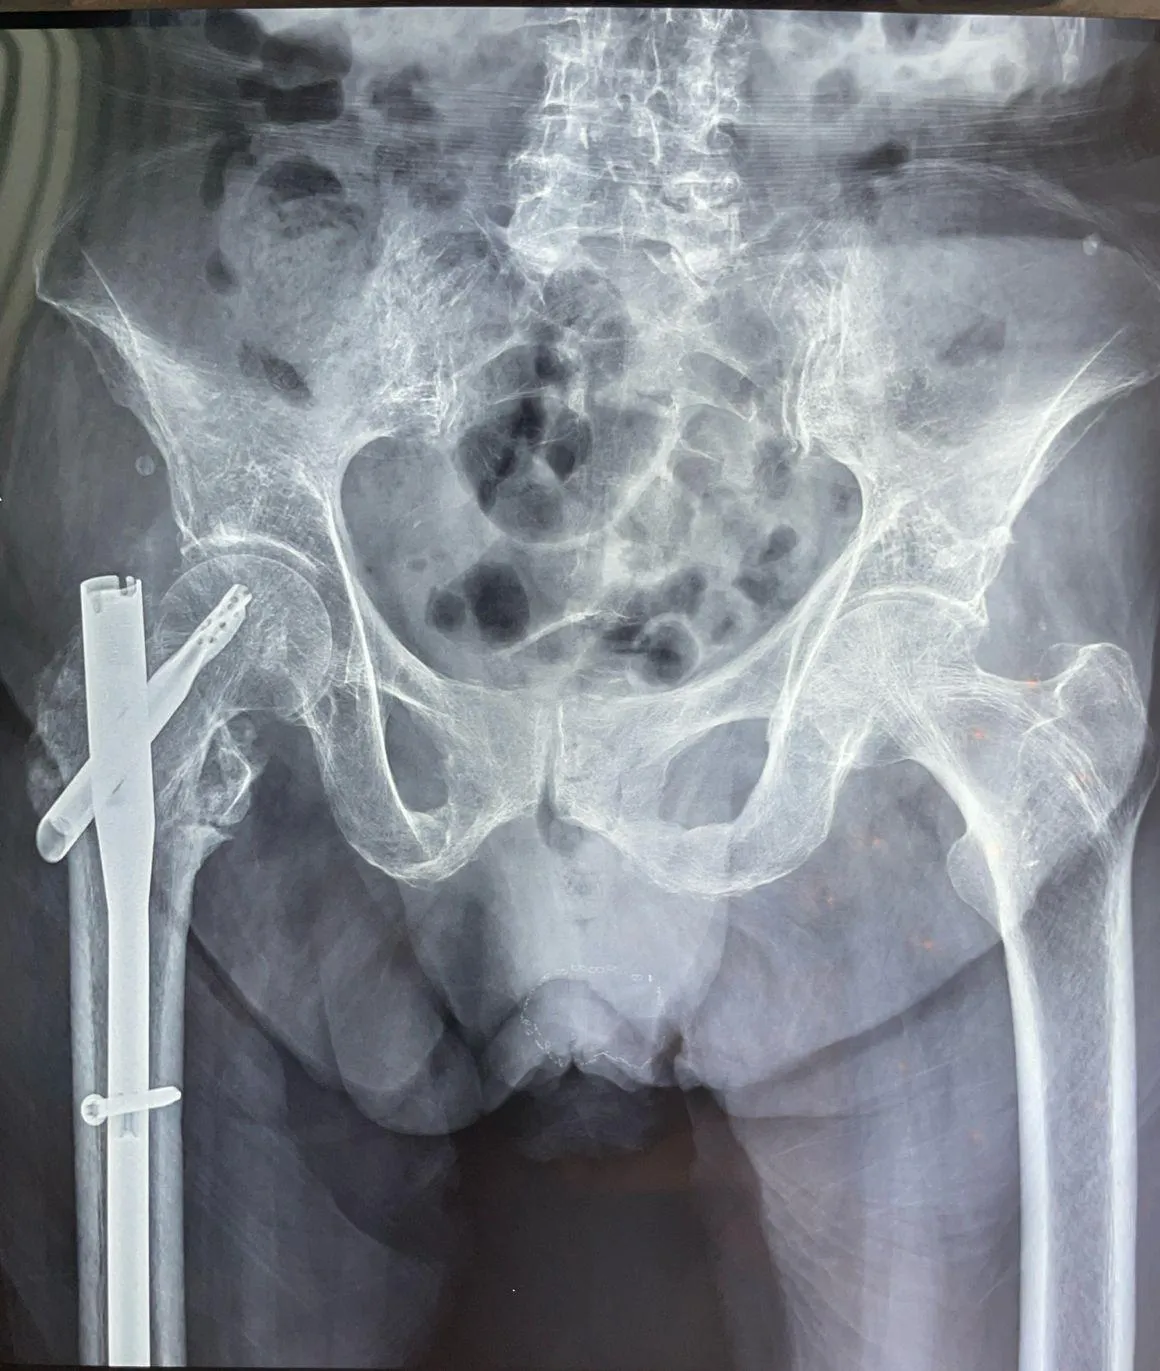

Fractura Antigua

Fractura antigua de cadera tratada con prótesis de doble movilidad

Fractura de cadera de larga evolución. Se realizó procedimiento quirúrgico con colocación de prótesis de doble movilidad.